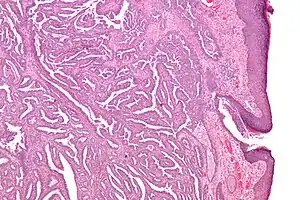

| Micrograph of a nipple adenoma. H&E stain. | |

Once excised, the macroscopic appearance of nipple adenomas is of a poorly defined nodular mass. The microscopic appearance can be quite bizarre, and may be misinterpreted as a carcinoma. Nipple adenomas usually have a rounded outline at low magnification, and at higher magnification can be seen to consist of a haphazardly arranged mass of proliferating tubular structures composed of epithelial and myoepithelial cells within varying amounts of fibrous stroma. The epithelial cells are usually columnar, but the columnar epithelial cells can undergo apocrine or squamous metaplasia. Mitotic figures and necrosis are not commonly seen.[1]